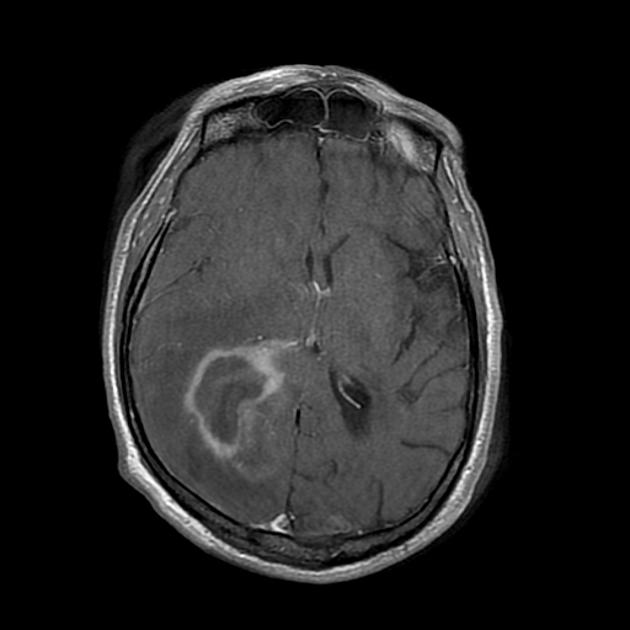

A detailed history and physical evaluation with particular attention to time course and nature of symptoms, followed by an MRI of the brain is the usual initial workup. The T1 MRI shows a hypointense or isointense lesion, and T2/FLAIR shows variable surrounding edema. T1/Gad shows homogenous enhancement without ring enhancement and lacking central necrosis. Ring enhancement occurs more often in immunocompromised patients.

MRI